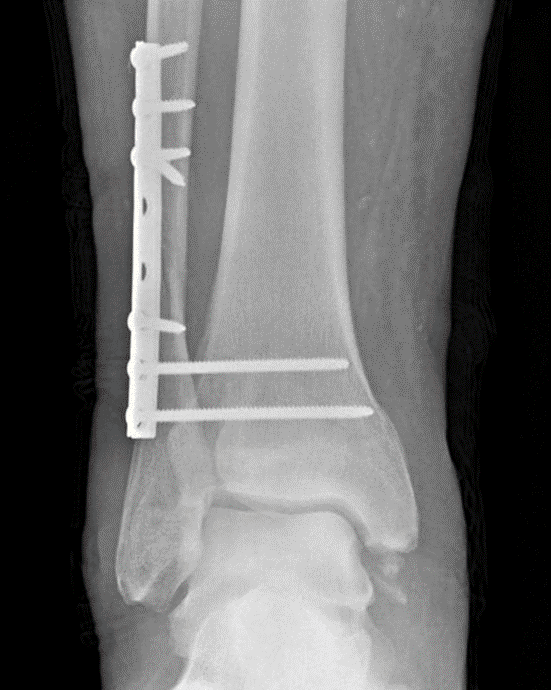

Postoperative radiograph in this patient showing fixation of the fibula and two syndesmotic screws.